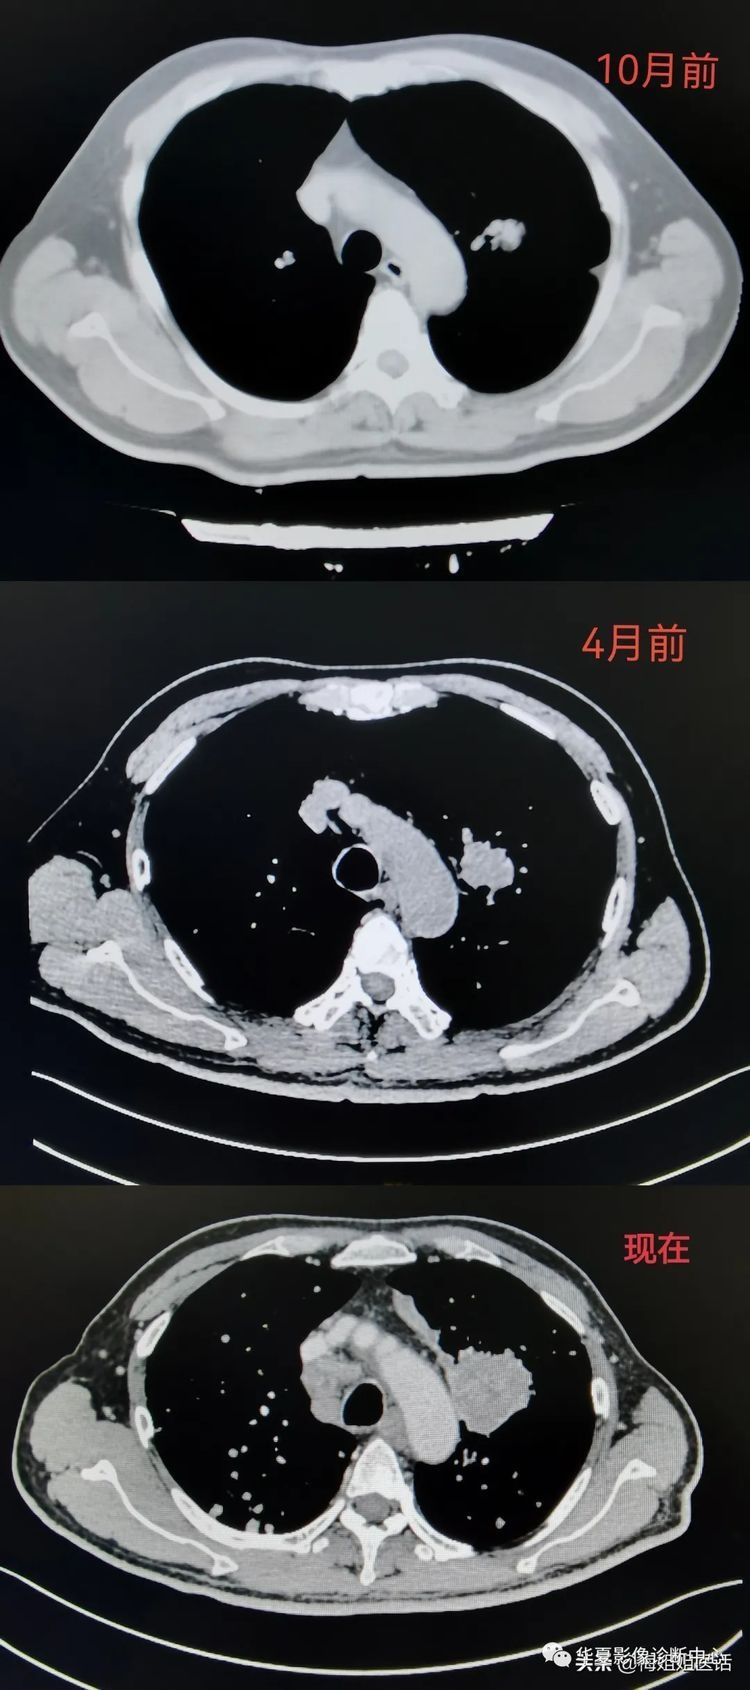

这位患者,10个月前,因为别的疾病检查胸部CT,偶然发现左肺肿块。报告考虑是肿瘤性病变。患者拒绝医生给予的检查治疗建议,回家中药治疗。

4个月前,患者再次复查胸部CT。结果显示:左肺肿块较前增大。双肺结节、纵隔、左肺门多发淋巴结显示。较前增多、增大,考虑肿瘤转移。患者仍拒绝进一步检查,继续中药治疗。

进医院后,经CT等检查,发现肿瘤较之前明显长大。并且颅内,双肺,肝脏,肾上腺等等均查见异常,考虑是肿瘤转移……

从肺部包块到肺癌,包块长大并出现肺内转移

上面三张CT影像图片,显示了患者从10个月前发现左肺病灶。病变逐渐长大并侵袭更多器官的影像变化过程。

看着患者正常的肺在这10个月里逐渐被像满天星一样星星点点的白色病灶蚕食。很有些遗憾。